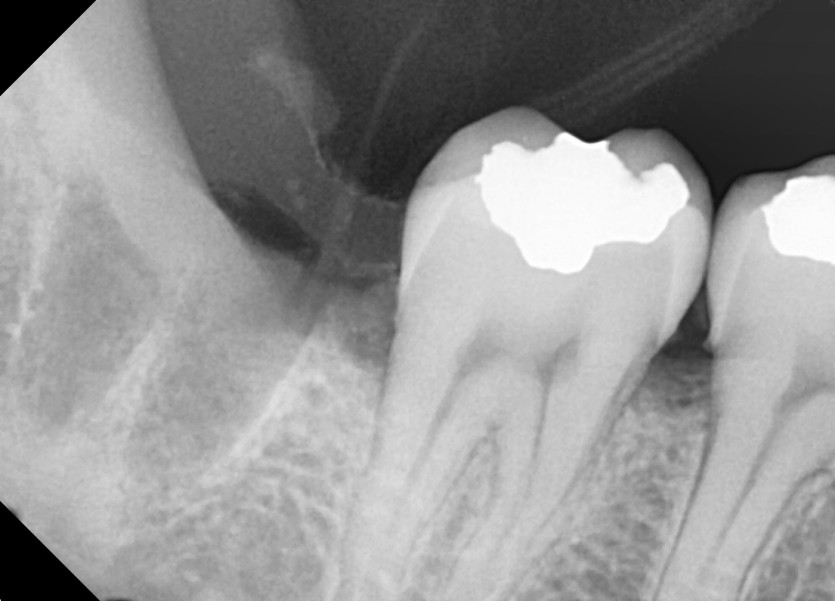

#38, 48 사랑니 발치

구강외과 전문의가 당일발치했습니다.